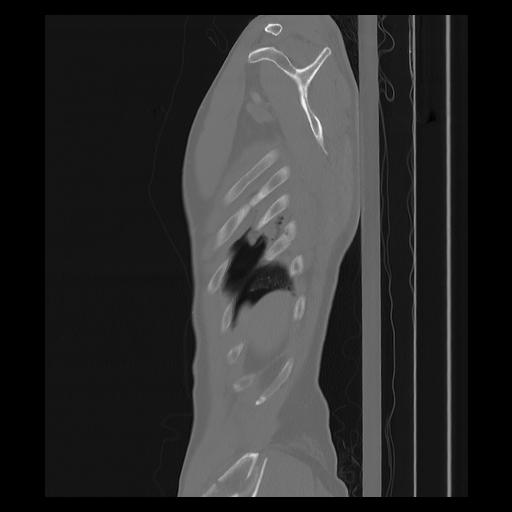

33 PULMON,CE,Sagittal,3.000,PULMON,Sagittal,